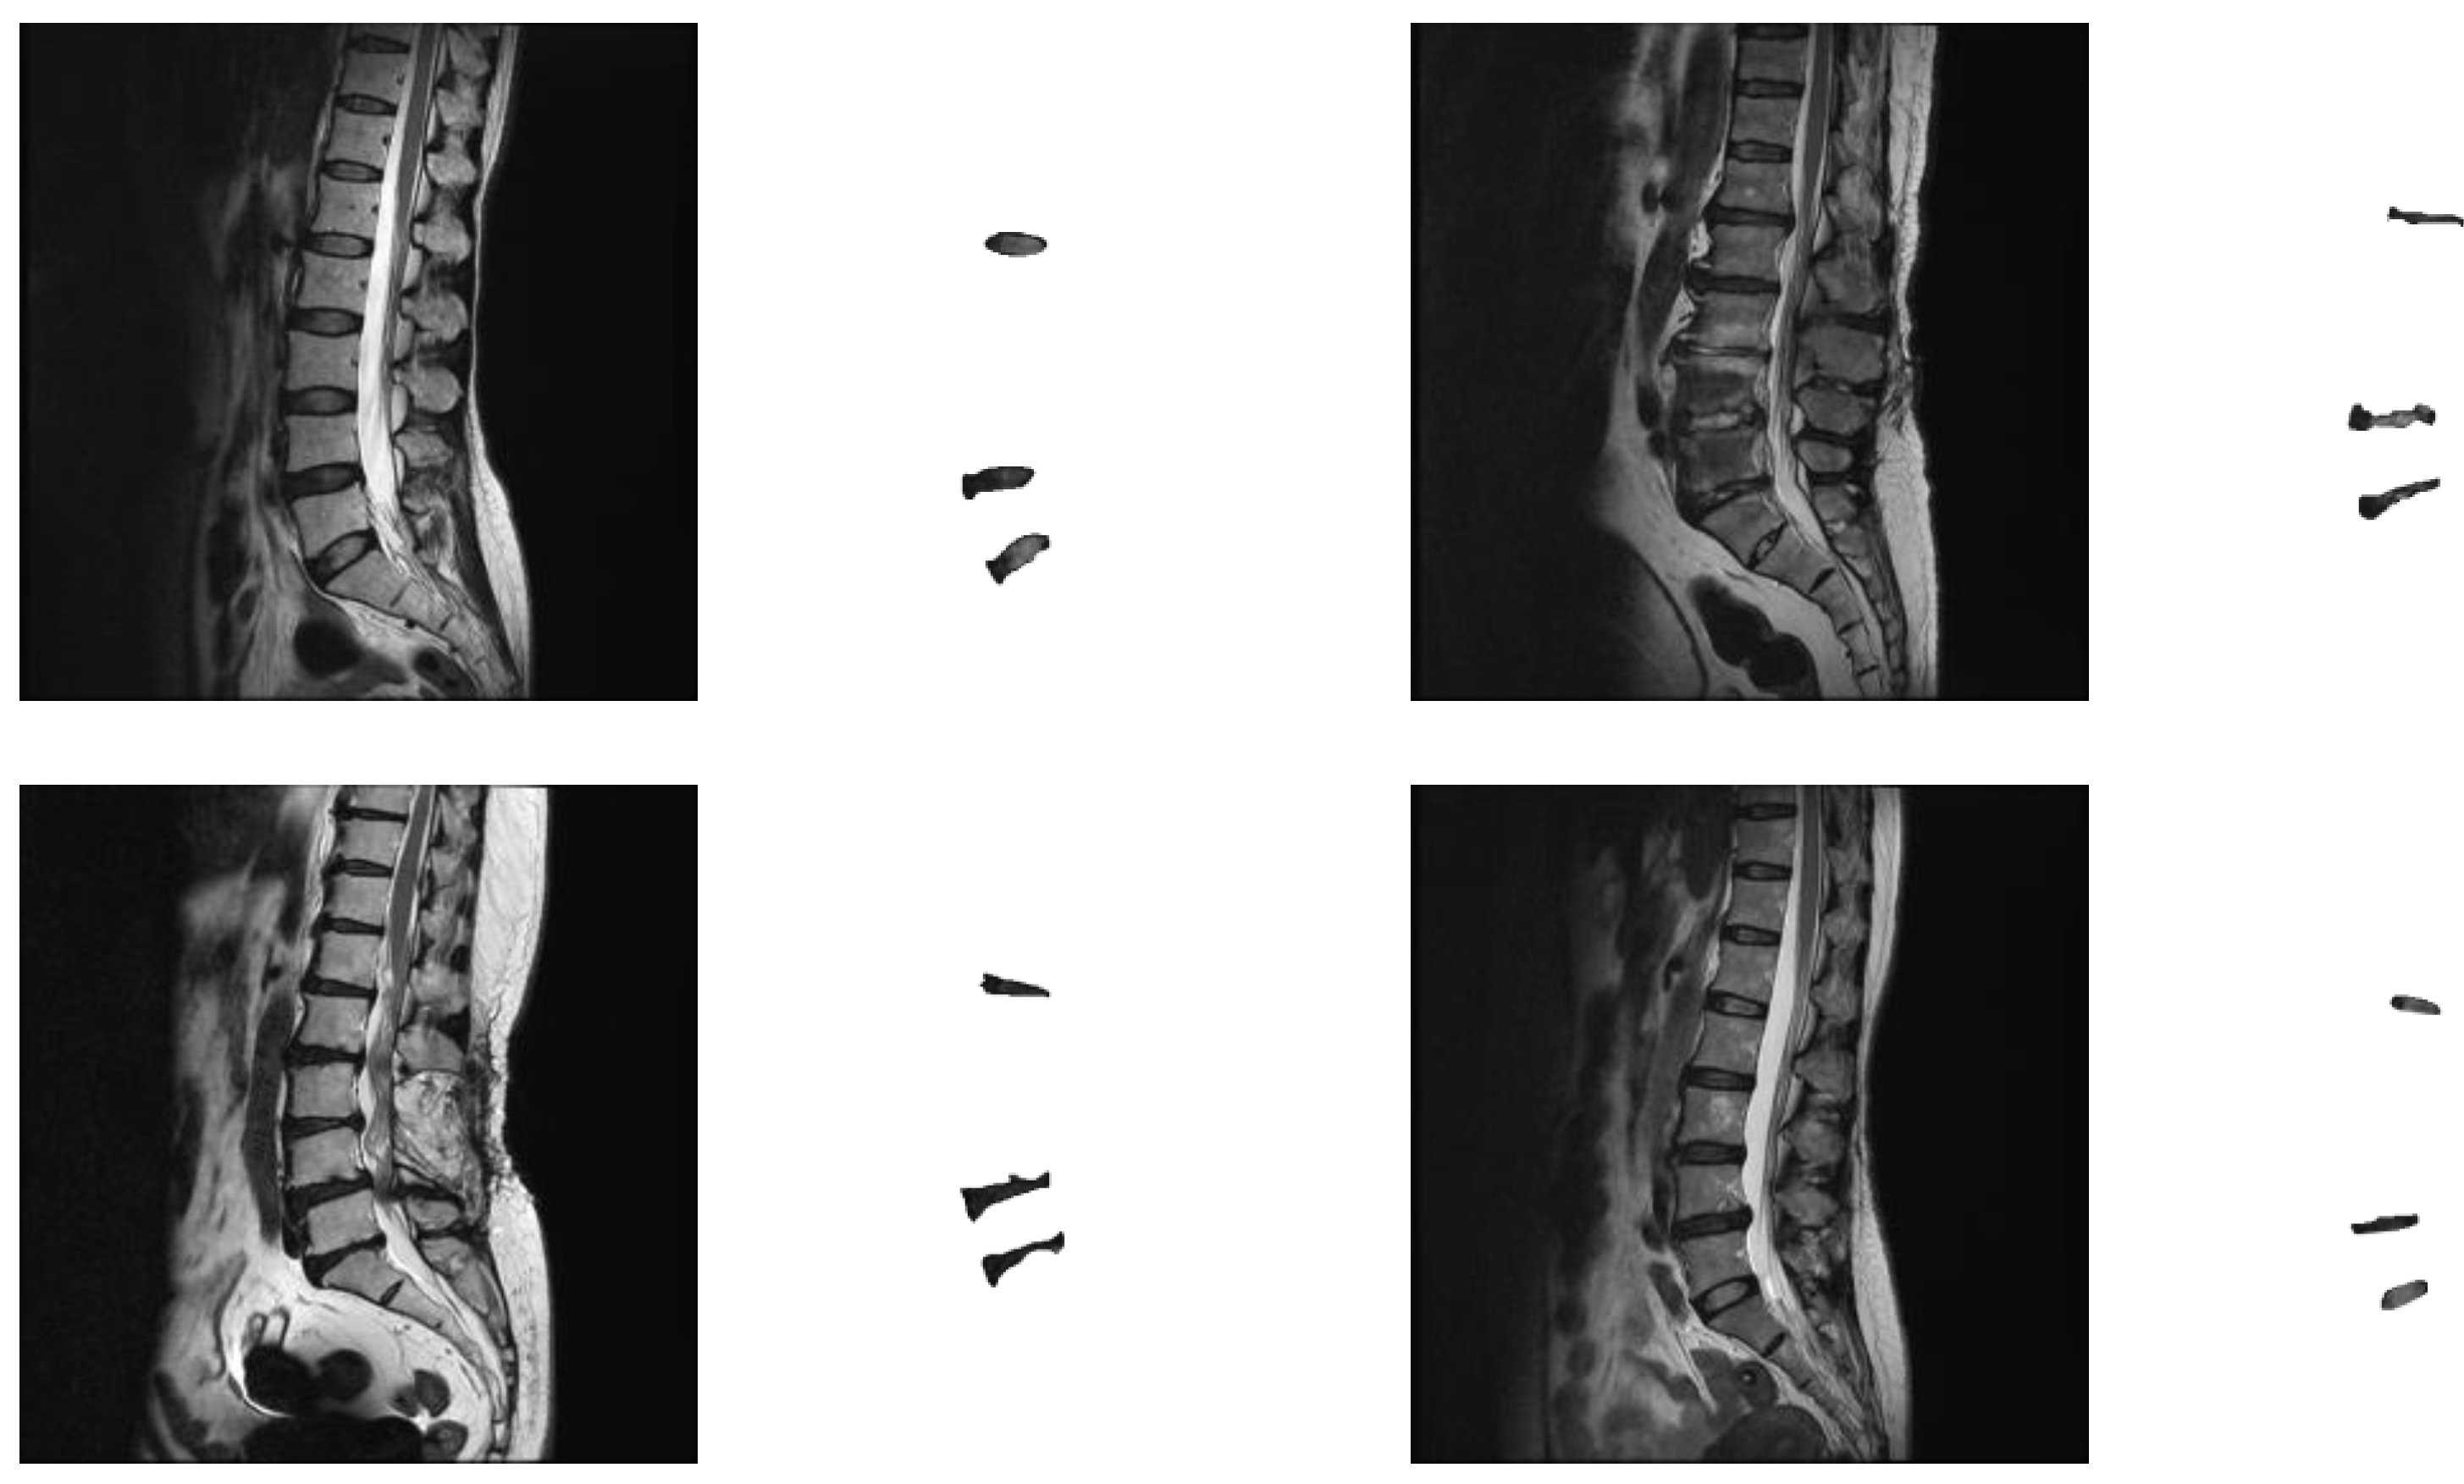

The number of experimental images is calculated based on the sample size estimated by the confidence interval [31]. If a 95% confidence interval is set and a standard deviation of 0.01 and a margin of error of 0.04% are used, then the most conservative sample size can be calculated, which is approximately 2400 images. The number of collected images, about 3000 images, exceeded the most conservative sample size required. The experimental images were randomly divided into a training set and a test set, which are 2674 and 308 images, respectively. Figure 1 shows some experimental image samples and corresponding manually labeled standard masks.

Figure 1. Experimental image samples and the corresponding manually labeled mask.